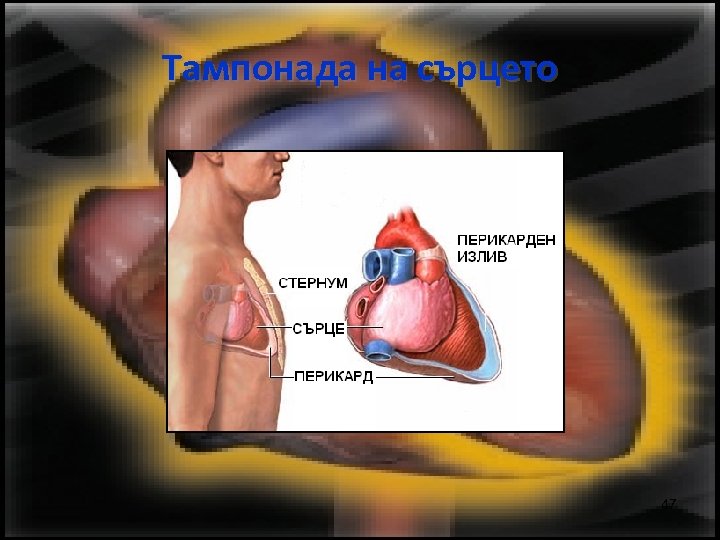

Тампонада на сърцето • Остро настъпващ излив на течности в перикардната кухина, поради което се затруднява диастолното пълнене на сърцето. • Намалената разтегливост директно води до намаляване на ударния обем на сърцето 46

Тампонада на сърцето 47

Тампонада на сърцето 48

Тампонада на сърцето 49